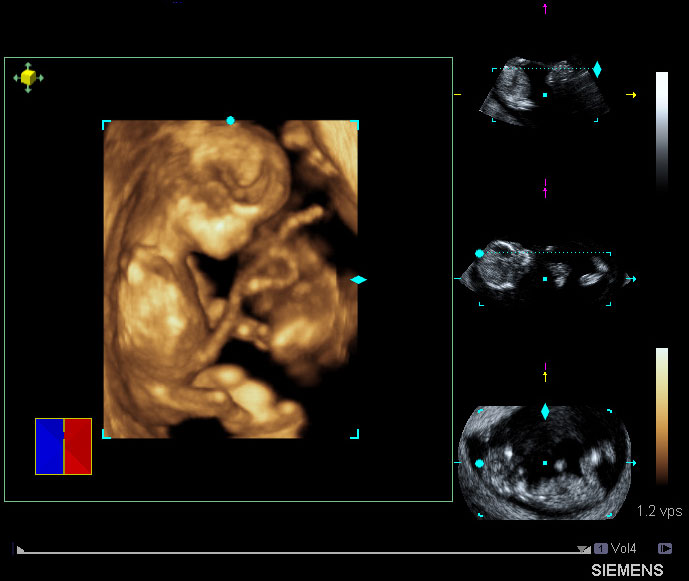

Широкое внедрение цифровых технологий в методы лучевой диагностики качественно и информационно изменили изображения исследуемых органов. Таким образом, получили широкое распространение методы трехмерного (объемного) получения и отображения данных медицинской визуализации. КТ стала первым методом, с помощью которого удалось создавать трехмерные реконструкции внутренних органов. Но теперь трехмерная визуализация возможна с помощью УЗИ, МРТ, рентгенографии, ангиографии и радионуклидных методов – т.е. всего спектра современных методов диагностики (Рис.2, Рис.3, Рис.4) [7, 10, 11]. В ближайшем будущем все исследования будут визуализироваться в виде трехмерного изображения, что является крайне важным для врачей.